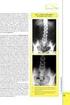

1 S.I.E.D. Società Italiana Endoscopia Digestiva La gastrostomia endoscopica percutanea a cura di: Mario Del Piano, Marco Ballarè SCDO Gastroenterologia, Azienda Ospedaliera Maggiore della Carità di Novara Introduzione In numerose patologie è assodata l utilità di effettuare un trattamento nutrizionale che, in presenza di un tratto gastrointestinale integro, andrebbe preferenzialmente eseguito per via enterale, per i minori costi e per ridurre l incidenza di complicanze (1-4). In passato, gli accessi per la nutrizione enterale erano costituiti essenzialmente dal sondino naso-gastrico e dalla gastrostomia o digiunostomia chirurgica. Nel 1980 è stata introdotta la gastrostomia endoscopica percutanea (PEG) come alternativa all approccio chirurgico (1.2). Più recentemente, la digiunostomia endoscopica percutanea diretta (DPEJ) è stata introdotta come alternativa alla PEG, quando quest ultima sia non eseguibile o controindicata (5,6). Tra le alternative non chirurgiche, va segnalata la possibilità di posizionare gastrostomie con tecnica di radiologia interventistica (7). Indicazioni Il posizionamento di una PEG è indicato in tutti i pazienti con tratto gastrointestinale integro ma incapaci di assumere un adeguato introito calorico per via orale (3,4). Nel porre indicazione ad una PEG, si deve inoltre prendere in considerazione il tempo per cui dovrà essere proseguita la nutrizione enterale: non è indicato il posizionamento di una PEG per esigenze nutrizionali in presenza di una malattia incurabile e ad andamento rapidamente progressivo, oppure quando è prevedibile che la nutrizione enterale sia necessaria per un breve periodo (convenzionalmente inteso come inferiore a 30 giorni). In tal caso è invece indicato l utilizzo del sondino naso-gastrico (3,4). 1

2 Le indicazioni più comuni per il posizionamento di una PEG sono le seguenti: malattie neurologiche post-traumatiche, degenerative, neoplastiche, vascolari, congenite neoplasia della cavità orale, della faringe, della laringe ed esofago. Al di fuori delle indicazioni nutrizionali, la PEG può essere utilizzata a scopo decompressivo gastrico nelle occlusioni. La DPEJ trova indicazione in tutti i casi in cui è necessario un accesso per la nutrizione enterale e la PEG non è eseguibile per difficoltà tecniche (vedi più avanti) oppure controindicata (ad es., in presenza di gastroparesi) (5,6). Controindicazioni Controindicazioni assolute alla PEG la presenza di una severa coagulopatia non correggibile oppure l impossibilità di ottenere una soddisfacente transilluminazione gastrica per l interposizione di un organo (fegato, colon), per la presenza di ascite, per esiti di precedente chirurgia gastrica, per obesità (3,4,8,9). Controindicazioni relative sono la presenza di sepsi, di malattie neoplastiche, infiammatorie ed infiltrative delle parete gastrica o addominale (3,4,8,9). Ovviamente, le controindicazioni all esecuzione di un esame endoscopico del tratto digestivo superiore sono parimenti controindicazioni al posizionamento di una PEG (3,4). Materiali e tecniche Per il posizionamento di una PEG occorre disporre di una sala endoscopica ampia ed attrezzata per l esecuzione di endoscopie del tratto digestivo superiore: tuttavia, in caso di necessità, la PEG può essere effettuata al letto del paziente. La metodica può essere eseguita in sedazione cosciente con anestesia locale dell orofaringe con lidocaina spray e anestesia locale della parete addominale con lidocaina iniettabile. In una minoranza dei casi, è preferibile eseguire l esame in anestesia generale con intubazione oro-tracheale. Il posizionamento di una PEG deve essere sempre preceduto dall esecuzione di una indagine endoscopica completa del tratto digestivo superiore per escludere patologie che possono compromettere la buona riuscita della procedura. Anche al termine, il corretto posizionamento della sonda va controllato endoscopicamente. Tra i vari metodi proposti nel corso degli anni (1,2), il metodo pull è quello che ha ottenuto la maggiore diffusione. Esso prevede l introduzione di un filo di seta o di materiale sintetico nello stomaco, attraverso un ago introdotto oltre i piani muscolo-cutanei della parete addominale dopo anestesia locale ed esecuzione di un incisione della cute con bisturi. Il punto di penetrazione dell ago viene scelto mediante la palpazione e la transilluminazione eseguita da un endoscopio, che permette anche, con l insufflazione forzata, una distensione della cavità gastrica che consenta una miglior adesione tra parete gastrica anteriore e parete addominale. Il filo viene quindi catturato con un ansa 2

3 la gastrostomia endoscopica percutanea da polipectomia ed estratto dalla cavità orale retraendo il gastroscopio. La sonda da gastrostomia viene quindi legata al filo che viene retratto fino ad ottenere la fuoriuscita della sonda dalla parete addominale. Il metodo push utilizza, al posto del filo di seta, una guida metallica flessibile sulla quale viene avanzata la protesi. Il metodo introducer si basa invece sulla tecnica utilizzata per il posizionamento dei cateteri venosi centrali: esso infatti prevede l introduzione nello stomaco di un corto filo guida metallico sul quale, dopo successive dilatazioni, viene inserito un introduttore che permette il posizionamento di un catetere a palloncino tipo Foley. I metodi pull e push sono sovrapponibili sia per quanto riguarda i costi che per risultati e complicanze. Il metodo introducer, soprattutto se associato al sistema degli ancoraggi che riduce alcune complicanze insite in questa metodica, risulta più indaginoso e costoso, ma si rivela prezioso nei casi in cui la presenza di una stenosi faringo-esofagea renda difficoltoso il transito dell estremità svasata della sonda gastrostomia utilizzata dalle altre due tecniche. Tra i vari kit disponibili in commercio, è preferibile scegliere le sonde traction removal (cioè rimuovibili senza bisogno dell endoscopia) e di ampio calibro (18-20 Fr, meno soggetti ad ostruzione). Prima dell esecuzione della PEG, è preferibile effettuare una profilassi antibiotica, che riduce significativamente le complicanze infettive: viene solitamente raccomandata una profilassi a base di penicilline (10,11). La protesi va collegata ad un sacchetto a caduta per valutare il ristagno gastrico e l eventuale insorgenza di complicanze precoci. La nutrizione enterale può essere avviata il giorno successivo al posizionamento, in presenza di un ristagno < cc /24 ore. Complicanze Le complicanze della PEG sono relativamente infrequenti, anche se i dati della letteratura riportano una morbilità compresa tra il 3 ed il 17% ed una mortalità del 0,3-1,3% (4,8,9). Quest ampia variabilità è probabilmente legata alla diversa epoca in cui sono stati effettuati gli studi, alle modalità di raccolta dei dati (retrospettiva o prospettica), alla durata dei follow-up, ai diversi criteri di selezione dei pazienti, all esperienza degli operatori ed ai diversi criteri classificativi (8,9). Per ovviare a questi inconvenienti, è stato proposto di classificare le complicanze in maggiori (a rischio di morte oppure che necessitano l intervento chirurgico o comunque l ospedalizzazione) e minori, distinguendole inoltre in complicanze legate alla procedura endoscopica, infettive, meccaniche e nutrizionali. Seguendo tali criteri classificativi, le complicanze maggiori risultano essere del 1,2%, le minori del 12,5% (8,9). La complicanza più frequente è rappresentata dall infezione della cute intorno alla stomia, che va dal semplice eritema cutaneo fino all ascesso ed alla fasciite necrotizzante. Più raramente sono state descritte peritoniti, emorragie, perforazioni intestinali, fistole gastrocoliche. Una complicanza legata alla nutrizione è il reflusso gastroesofageo che, in casi rari, può arrivare fino all aspirazione massiva nelle vie aeree. 3